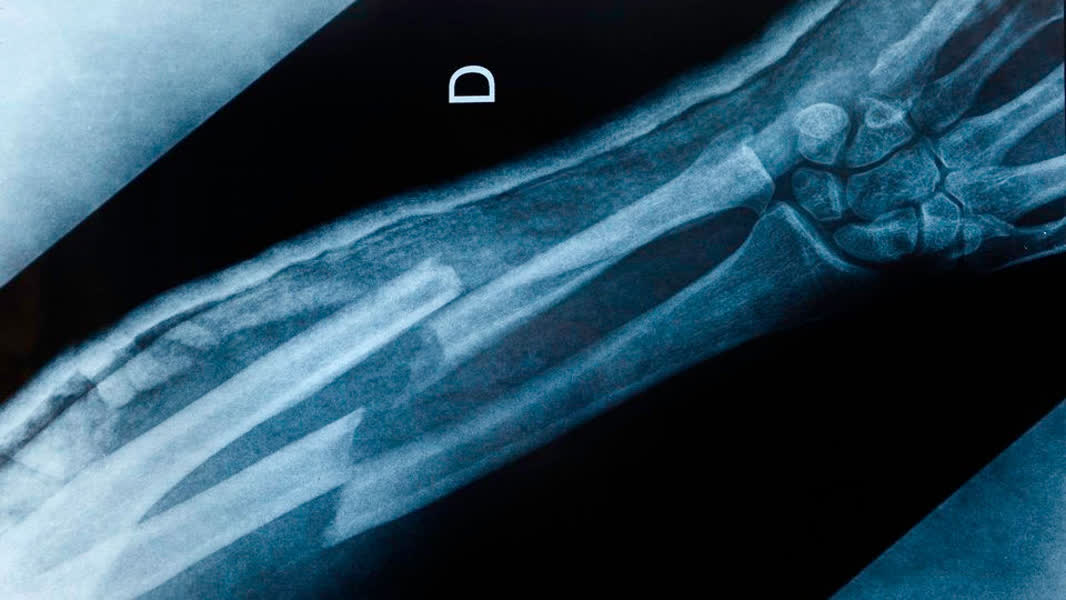

VieCuri: Meer mensen met botbreuken

Op de spoedeisende hulp van het VieCuri ziekenhuis komen vanwege het winterse weer en de gladheid meer mensen met botbreuken binnen. Dat meldt 1Limburg. Het ziekenhuis, met vestigingen in Venlo en Venray, ziet een lichte toename van het aantal patiënten met botbreuken. Er zijn nog geen mensen met onderkoelingsverschijnselen door de vrieskou op de spoedeisende hulp beland.

VieCuri is niet het enige ziekenhuis dat een toename van drukte merkt. Ook Sint Jans Gasthuis merkt dat er meer incidenten zijn door gladheid. Daar komen vooral mensen met een gebroken pols of heup op de spoedeisende hulp terecht.

Patiënten met die botbreuken moeten ook in het Roermondse Laurentius Ziekenhuis een bezoek brengen aan de spoedeisende hulp en de gipskamer. Maandag ging het om 20 patiënten, dinsdag zelfs 32 en woensdagochtend waren dat er 4. "Bij gladheid zijn er altijd patiënten met botbreuken, maar met name dinsdag waren dit er extreem veel", laat het ziekenhuis weten.